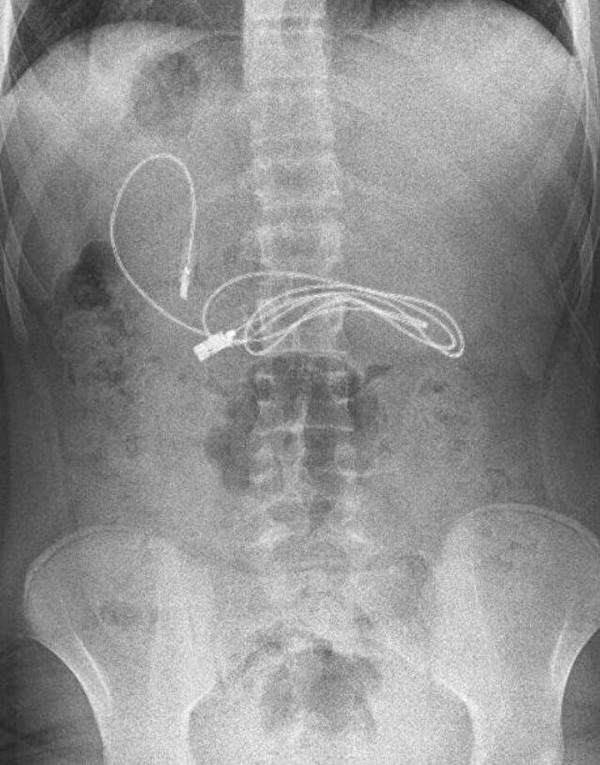

Diyarbakır'da kusma ve bulantı şikayetiyle hastaneye giden 15 yaşındaki erkek çocuğunun çekilen röntgeninde, midesinde şarj kablosu ve toka olduğu tespit edildi. Bunun üzerine çocuk, ambulans ile Fırat Üniversitesi Hastanesi'ne sevk edildi. Üniversitenin Çocuk Gastroenteroloji Hepatoloji ve Beslenme Bilim Dalı Başkanı Prof. Dr. Yaşar Doğan ve ekibi tarafından yapılan endoskopik işlemle çocuğun midesindeki kablo ve toka başarıyla çıkarıldı.Tedavisinin ardından sağlığına kavuşan çocuk taburcu edildi.

Ameliyatı gerçekleştiren Prof. Dr. Yaşar Doğan, kablonun bir ucunun ince bağırsağa geçmesi nedeniyle zorlandıklarını ifade ederek, “Hastanın kusma ve karın ağrısı şikayetleri olması üzerine sağlık kuruluşuna başvurulmuş.

Orada yapılan incelemelerde hastanın midesinde kablo tespit edilmesi üzerine bize danışıldı. 112 aracılığıyla hastaya gerekli işlemi yapıp yapmayacaklarını bize sordular. Biz de hastayı bize gönderebileceklerini kendilerine ilettik. Hasta bize geldikten sonra ön hazırlık yapıldı ve gerekli olan açlık süresinin ardından hastaya endoskopik işlem yapıldı. Endoskopik işlemle midedeki kablo çıkarıldı. Kabloyu çıkarırken açıkçası zorlandık, çünkü kablonun bir ucu ince bağırsağa geçmişti. İşlem başarılı bir şekilde sonlandırıldıktan sonra hasta sağlıklı bir şekilde evine gönderildi” dedi.